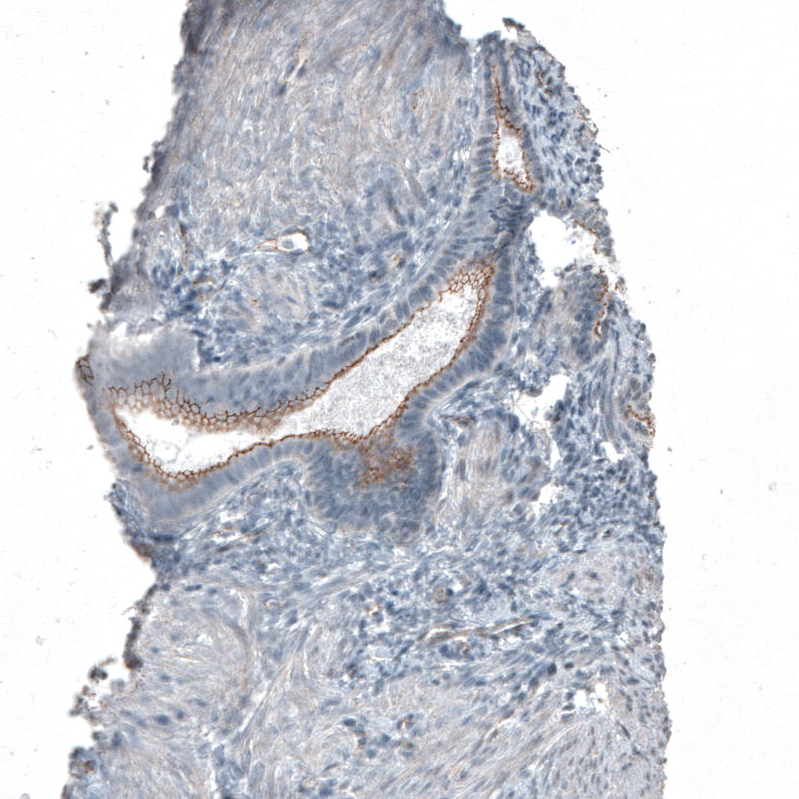

Immunohistochemical staining of human endometrium shows moderate membranous positivity in glandular cells.